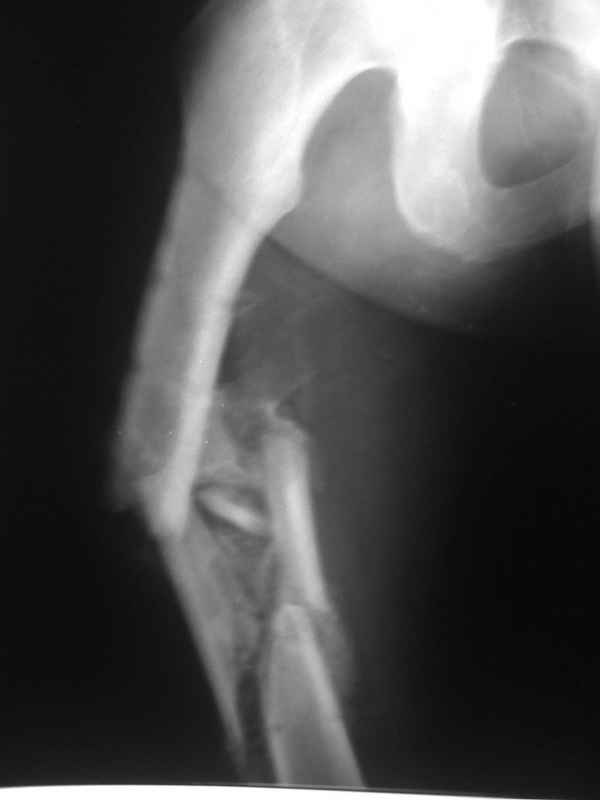

Re: Неправильно срастающийся оскольчатый перелом бедра